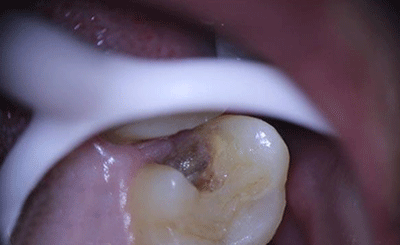

术前显微镜影像

注1:黄褐色为龋损牙体组织。

2:红色为出血点为牙髓组织(俗称牙神经),去腐未净时牙髓组织外露。